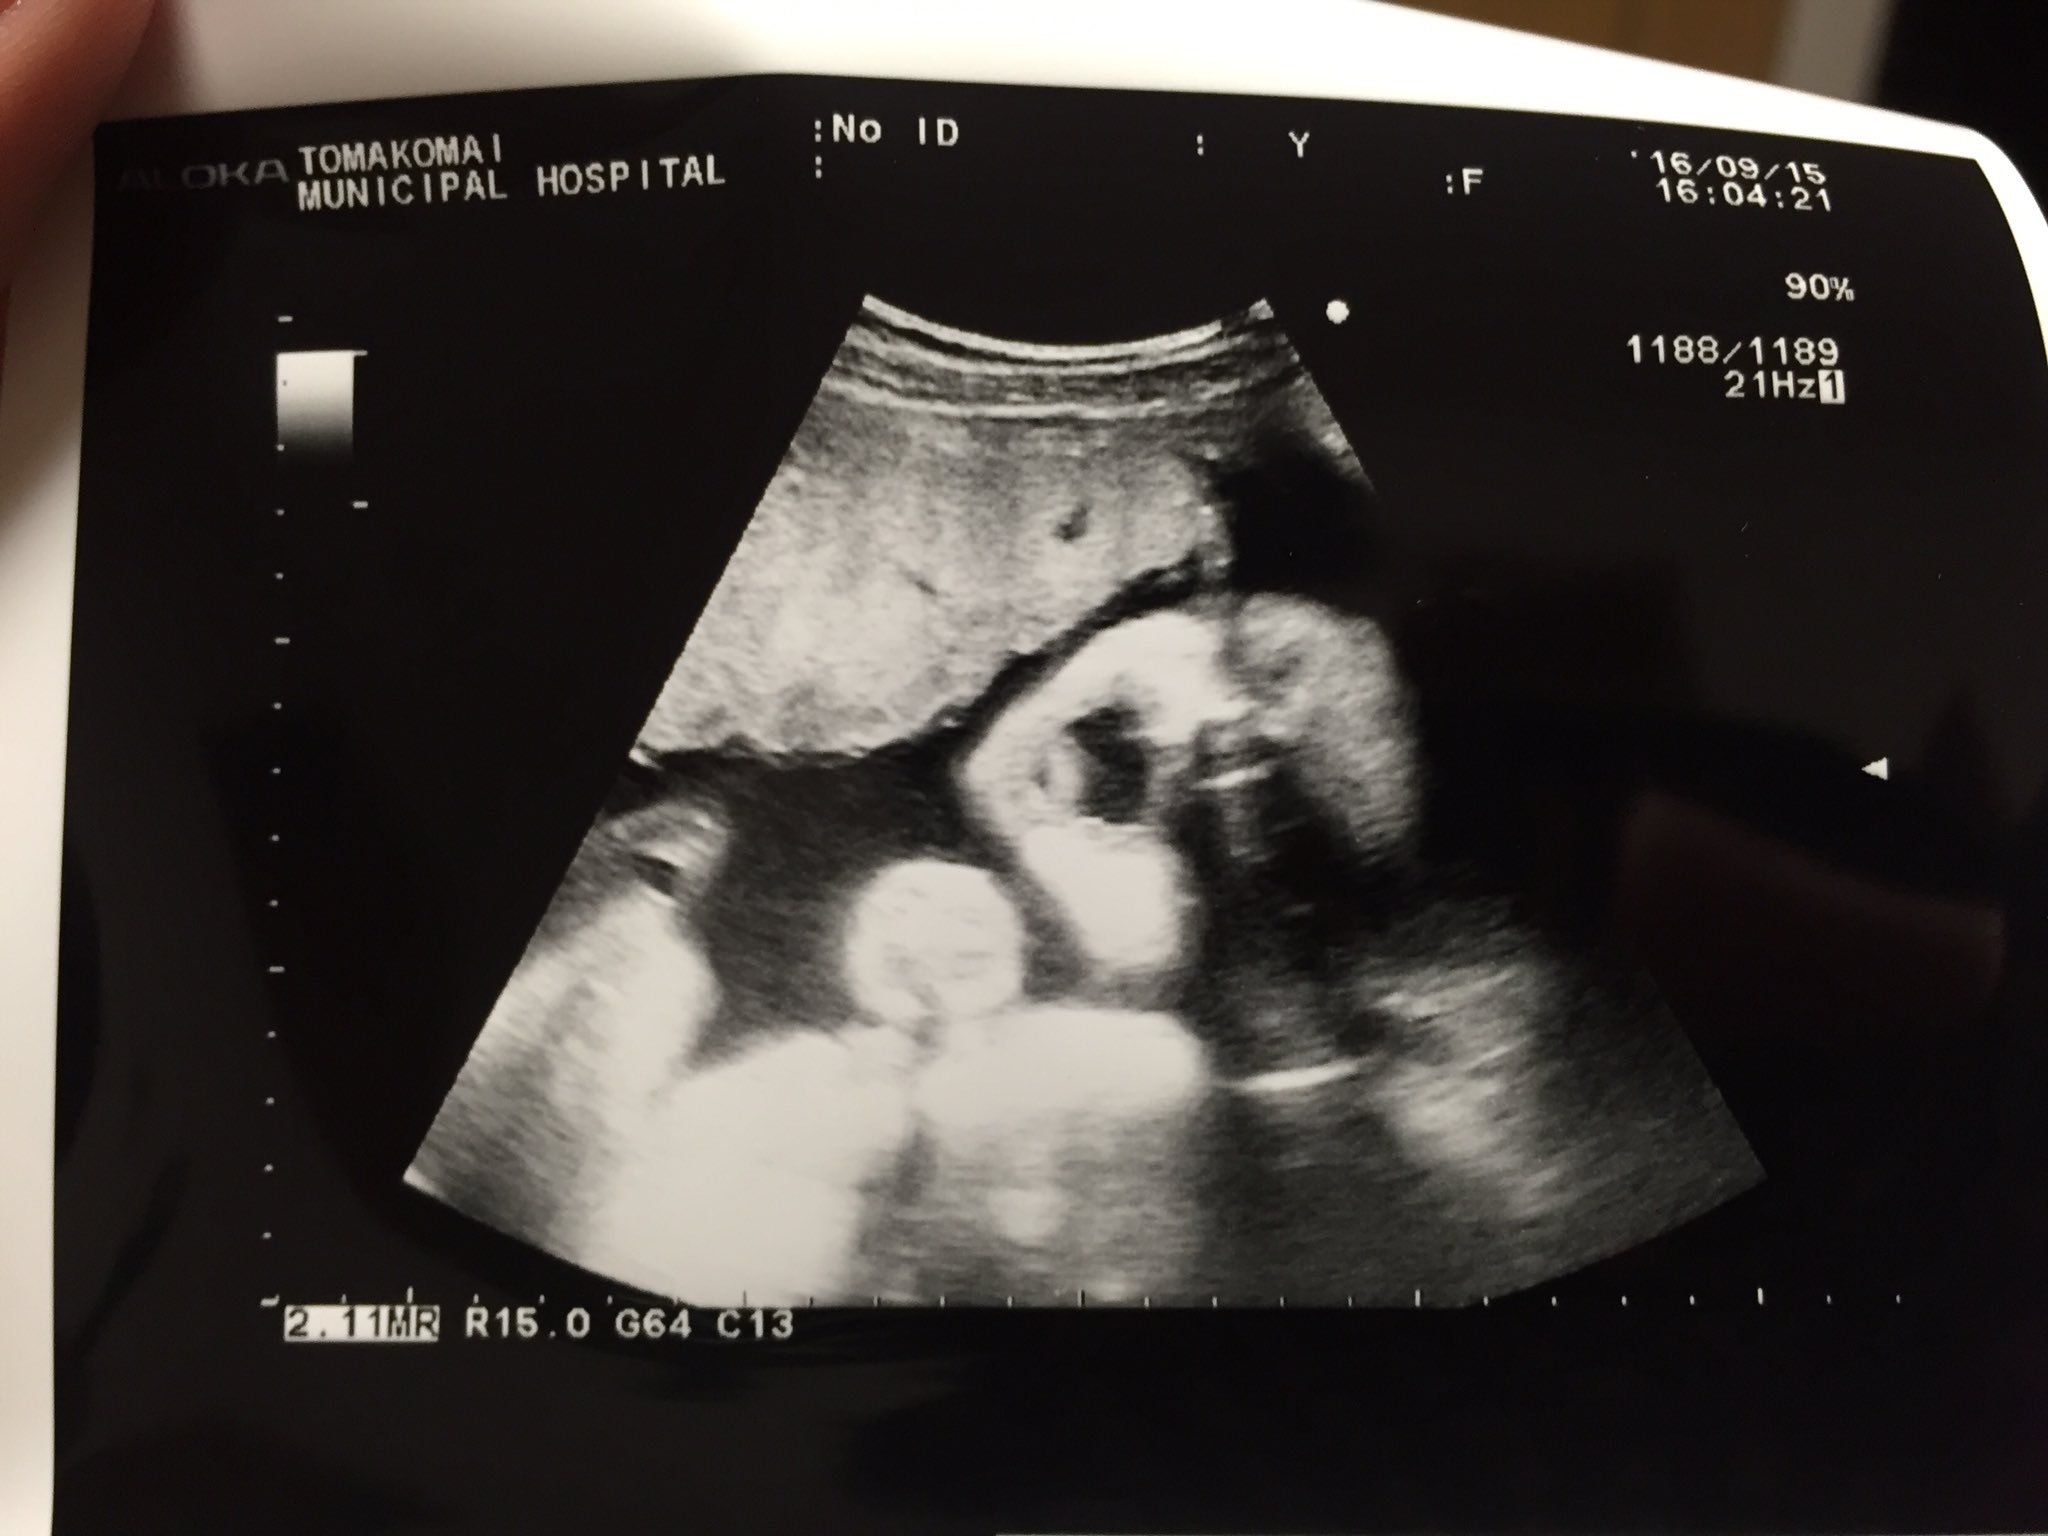

胎児って、あくびしますか・・? この前の27週の検診で、赤ちゃんがものすごく 大きく口を開けて、あくびしているのが見えたのですが、 (看護婦さんも「アクビしているね~」と言いましたが・・) でも、羊水の中にいて、あくびなんて出るものでしょうか?妊娠週 33w5d 33w5d 頭785㎜ おなか290㎜ 大腿骨61㎜ 1970g。 今回は胎児スクリーニング。 赤ちゃんの臓器に異常がないか調べてくれます。 あくびをしている赤ちゃんが見れました♪ (*^^*) 出血もまだ時々あるので心配が絶えませんが赤ちゃんは元気なので

1512/1 28week 1Day Echo Ultrasound 8month※後半に重要な追記あり!赤ちゃんの超音波検査を記録した動画(4倍速)です。前回の検診に引き続き、4D赤ちゃんはあくびもよくしています。赤ちゃんの肺は肺胞液という液体で満たされているので、あくびをして羊水を飲んでも大丈夫♪ 妊娠後期29週 従来のエコーが格段に進化した検査装置で、静止画像ではなく、立体像が動画で見ることができ2Dエコーとは違って、体の内部ははっきり見えません。 4Dエコー(動画、赤ちゃんの動く様子を観察) 3Dエコーに時間の要素を加えて、動画にしたものが「 4Dエコー 」です。 赤ちゃんの表情や動く様子がリアルタイムに観察できます。 妊娠週を過ぎる

4dエコーは映像として映し出されるもので、赤ちゃんの動作を見ることができます。 あくびをする様子や、手を動かしているなどの仕草まで見ることができます。 3d/4dエコーのタイミング 3d/4dエコーのタイミングとしては妊娠週数15~32くらいが良いでしょう。 新生児 画像あり赤ちゃんのエコーが写真と、産まれた後の顔を比べてみると・・・全然似てない! ? 年4月18日 赤ちゃんのエコー写真を見ると、産まれてくる赤ちゃんの顔が見れるので幸せな気持ちになりますよね。 私も出産前は、5Dや6Dエコー